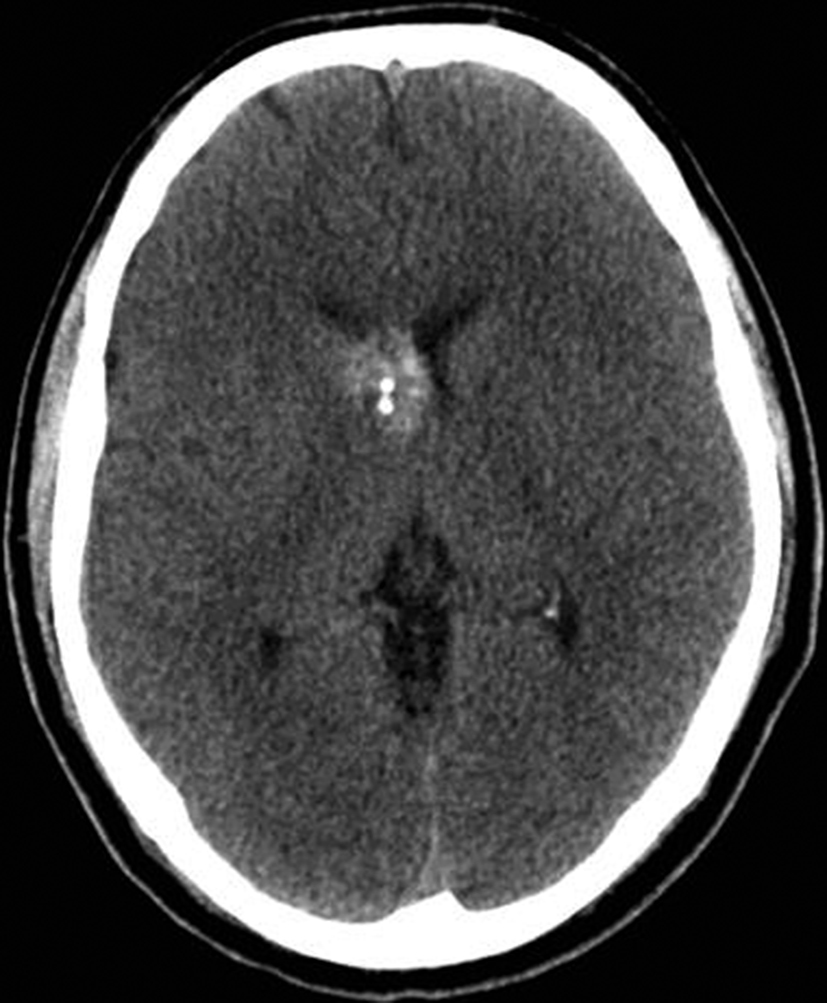

Con los hallazgos tomográficos, no se efectúan planteos diagnósticos y se realiza una resonancia magnética con la finalidad de obtener más datos semiológicos en busca de una aproximación diagnóstica. Se realizó el estudio por medio de secuencias T 1, FSE T 2, FLAIR, SWI y Difusión, en cortes axiales, FSE coronal y sagital T 1. Se realiza la administración de gadolinio DTPA en los tres planos. Se evidencia la lesión bien definida a nivel del ventrículo lateral derecho, que involucra al tronco del cuerpo calloso (Figura 2- C y 3- B). Presenta intensidad de señal heterogénea en secuencias T1 y T2 (Figura 3 y Figura 4). En secuencia ecogradiente se observa una señal marcadamente hipointensa y heterogénea, con un halo hipointenso bien definido (Figura 2- C). No presenta realce significativo tras la administración de Gadolinio (Figura 2- B) y en la secuencia de difusión no presenta restricción.

Figura 3

a y b) Imágenes sagitales T1, A. se observa la lesión a nivel del asta frontal de ventrículo lateral derecho y B. se evidencia la extensión al cuerpo calloso.

Figura 4

a y b) Imágenes coronales T2, Ay B. se evidencia la lesión con epicentro en el asta frontal del ventrículo lateral derecho y la extensión al cuero calloso.